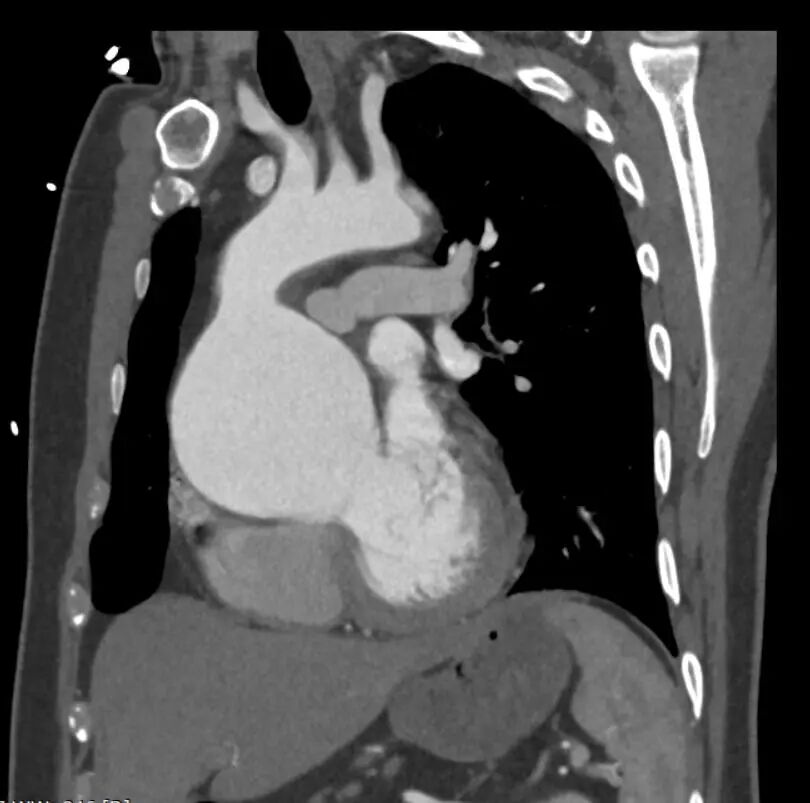

患者完成Bentall手术后进行CTA复查,CTA显示近端假腔隔绝,支架位置形态良好。

gore医疗怎么样「胸有乾坤」可调可控 分毫必争—GORE®TAG® 可主动调控胸主动脉覆膜支架治疗B型主动脉夹层伴升主动脉瘤病例报道_https://www.jmylbn.com_新闻资讯_第16张

术后3D重建